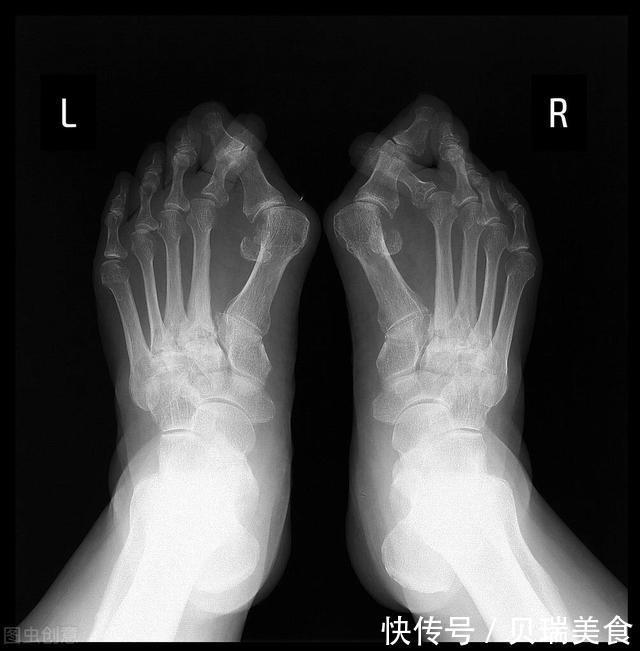

大拇|路医生说丨高跟鞋美女脚下的痛,得了“拇外翻”,该怎么办?

如果仔细观察不难发现,如今女性时尚点的鞋子大多都是“尖头”的,尤其是高跟鞋。这种尖头的鞋子的确可以让脚的外观轮廓显得更修长美丽,尤其是高跟鞋更能让女性的双腿显得修长,整体气质得到明显提升。但是,这种变美的同时,也是付出了代价的。那就是,我们的脚趾头受了罪,尤其是大拇脚指头。实际上,大脚趾的拇外翻畸形在女性群体中非常常见,即便是不穿高跟鞋的女性也有很多会患有拇外翻畸形。而且这种畸形大多数并不是一上来就非常严重,绝大多数拇外翻在一开始都是比较轻没有任何不舒服的,但是如果不注意,这种畸形就很可能会逐渐加重,导致足趾畸形加重,拇囊炎发作疼痛难忍,严重影响生活、工作和运动。那么,拇外翻到底是个什么病,又该如何治疗和保养呢?今天咱们就来聊一聊这个话题。#真相来了#1、啥叫拇外翻?

所谓的“拇外翻”,其实就是指:我们的大拇脚指头,在关节部位向外偏斜,而且超过正常生理范围的一种前足畸形。坊间老百姓也会管这个叫“大脚骨”。换句话说,就是:大拇脚指头过度的向外侧,也就是其他脚趾头的方向偏斜。这就让大拇脚指头根会向内侧突出,像突出来一块骨头一样。这就是拇外翻。如果拇外翻严重,或者因为外伤等情况加重,拇外翻突出骨头那部位红肿疼痛,这时候我们就管这个叫“拇囊炎”,也就是拇外翻最常见的因为疼痛不适的原因。2、为啥会得?